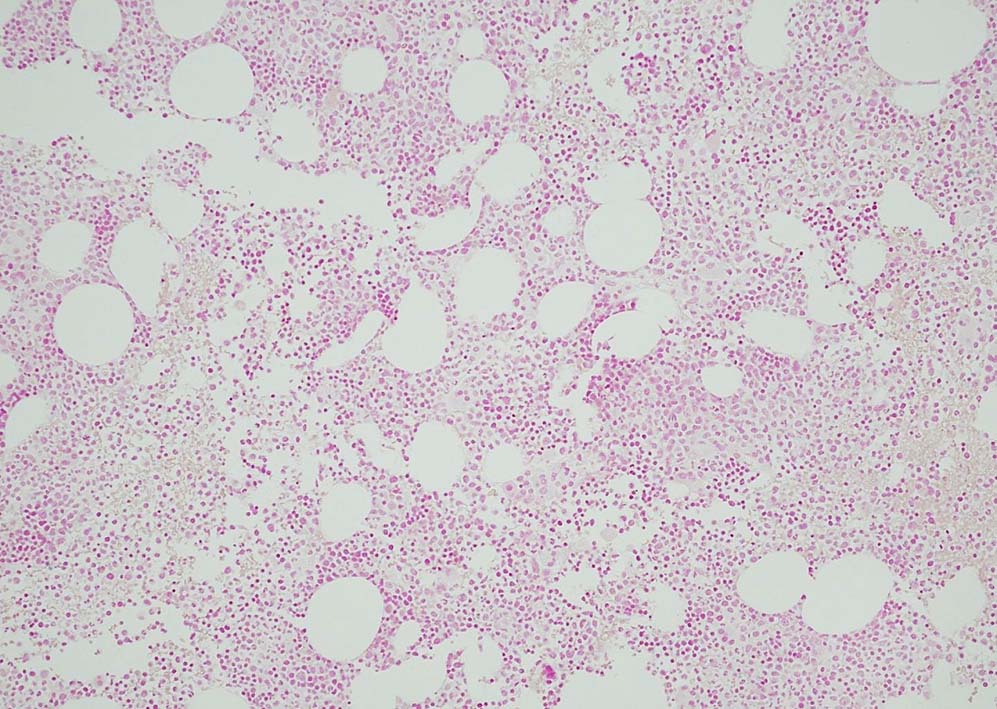

Megakaryopoiesis; Mgkは増加している. 多数の分離円形核巨核球が出現している. microMgkが増加している.

Myelogram: M/E = 1.77,Blast-M 5.2%, promyelo 7.0%, Myelo 11.4%, Meta 10.0%, Stab 5.4%, Seg 18.8%, Eo mature 0.6%, Ba mature 0.6% Mo 3.0%, Lympho 4.4%, Plasma 0.2 骨髄WT1 R 1.1x104